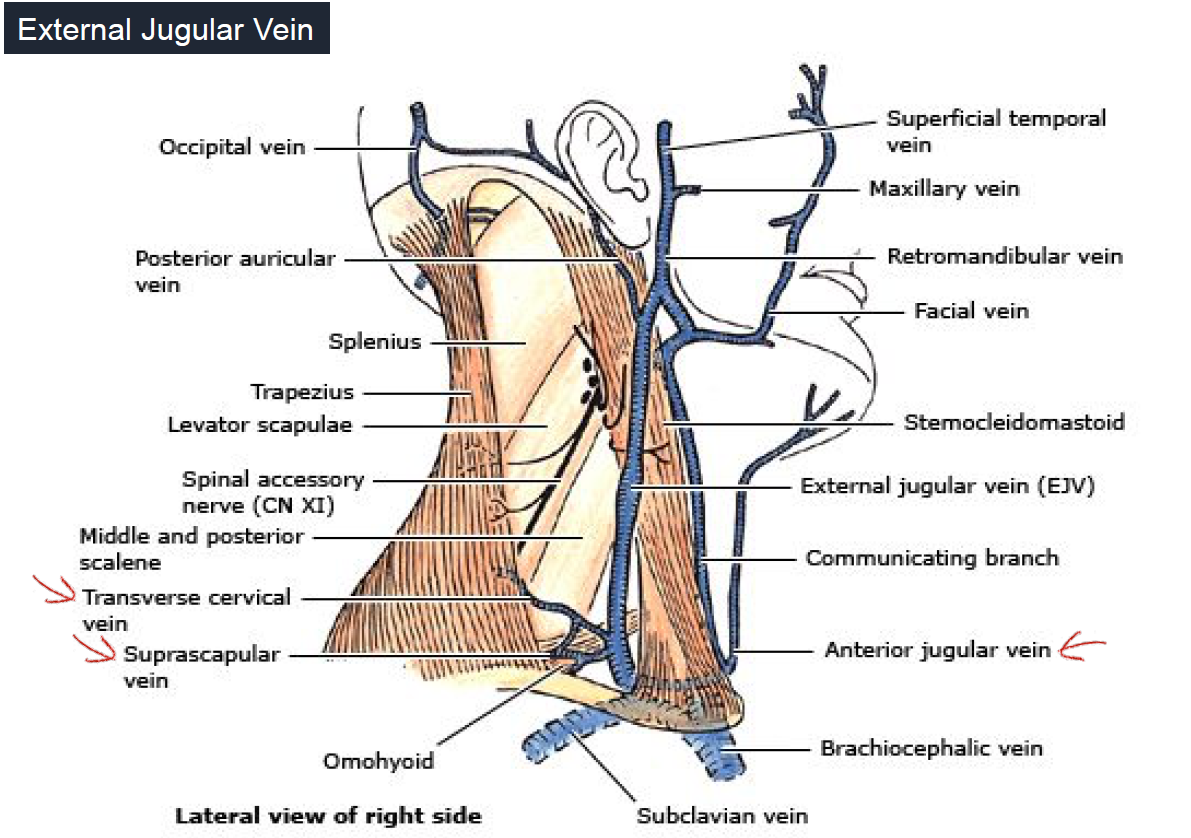

Vein

subclavian vein 在ant. scalene m. 上方

- Superficial temporal:

- Anterior to the Superficial temporal a.

- Joins the maxillary v. to form the

- retromandibular v.

- Middle temporal:

- Arises deep within the temporalis m. and fascia

- Joins the superficial temporal v. immediately before it passes inferior to the root of the zygomatic arch

- Anterior & Posterior deep temporal:

- Drain into the pterygoid plexus of veins

- Also communicate with the middle temporal v.

- Maxillary: *

- A short branch formed by a confluence of the pterygoid plexus of veins

- Joins the superficial temporal v. to form the retromandibular v.